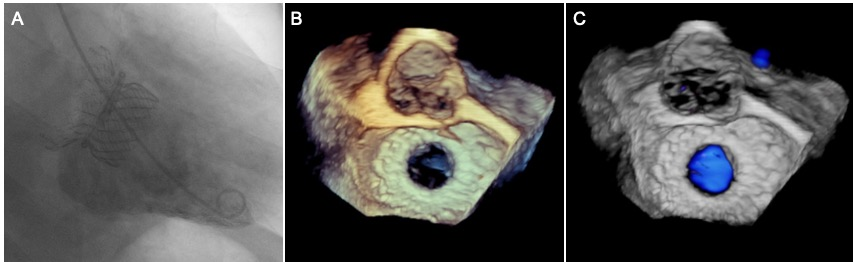

术后即刻造影和超声结果。左图:造影结果提示瓣膜工作良好,二尖瓣无反流;中图和右图:三维超声提示瓣膜工作良好,二尖瓣无反流。

手术如期进行。手术技术关键操作时间平均为60-90分钟,瓣膜反流立刻从术前的重度变为无反流,即刻效果和外科开胸换瓣相当,术中和术后无严重出血、无传导阻滞、无流出道梗阻,血压心率均平稳。